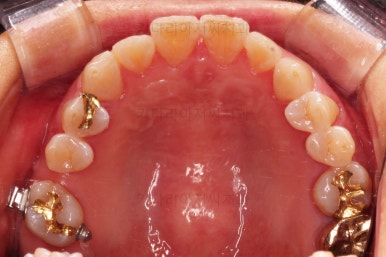

어금니를 뒤로 밀어주기 위해서 미니스크류와 브라켓, 철사를 이용해줘요.

중간중간 장치 디자인이나 미니스크류의 위치를 바꿔주기도 하고요.

점점 자리가 확보되어가는게 보이시죠?